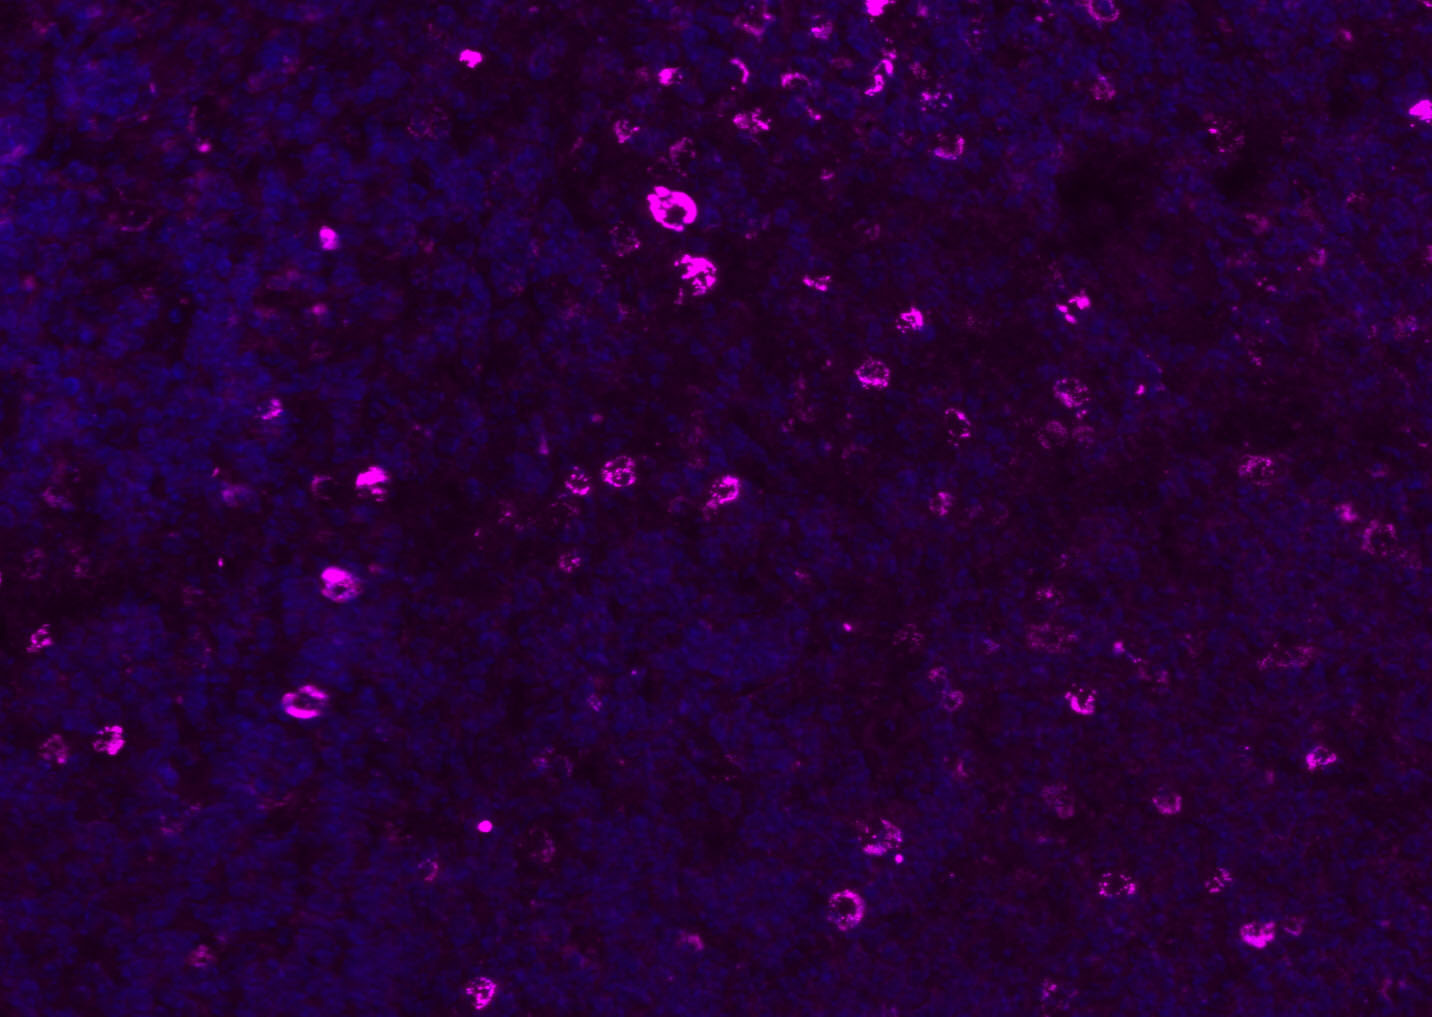

Tissue/cell: human lung carcinoma;4% Paraformaldehyde-fixed and paraffin-embedded;

Antigen retrieval: citrate buffer ( 0.01M, pH 6.0 ), Boiling bathing for 15min; Blocking buffer (normal goat serum,C-0005) at 37℃ for 20 min;

Incubation: Anti-CD8 Polyclonal Antibody, Unconjugated(bs-4914R) 1:200, overnight at 4°C; The secondary antibody was Goat Anti-Rabbit IgG, Cy3 conjugated(bs-0295G-Cy3)used at 1:200 dilution for 40 minutes at 37°C. DAPI(5ug/ml,blue,C-0033) was used to stain the cell nuclei